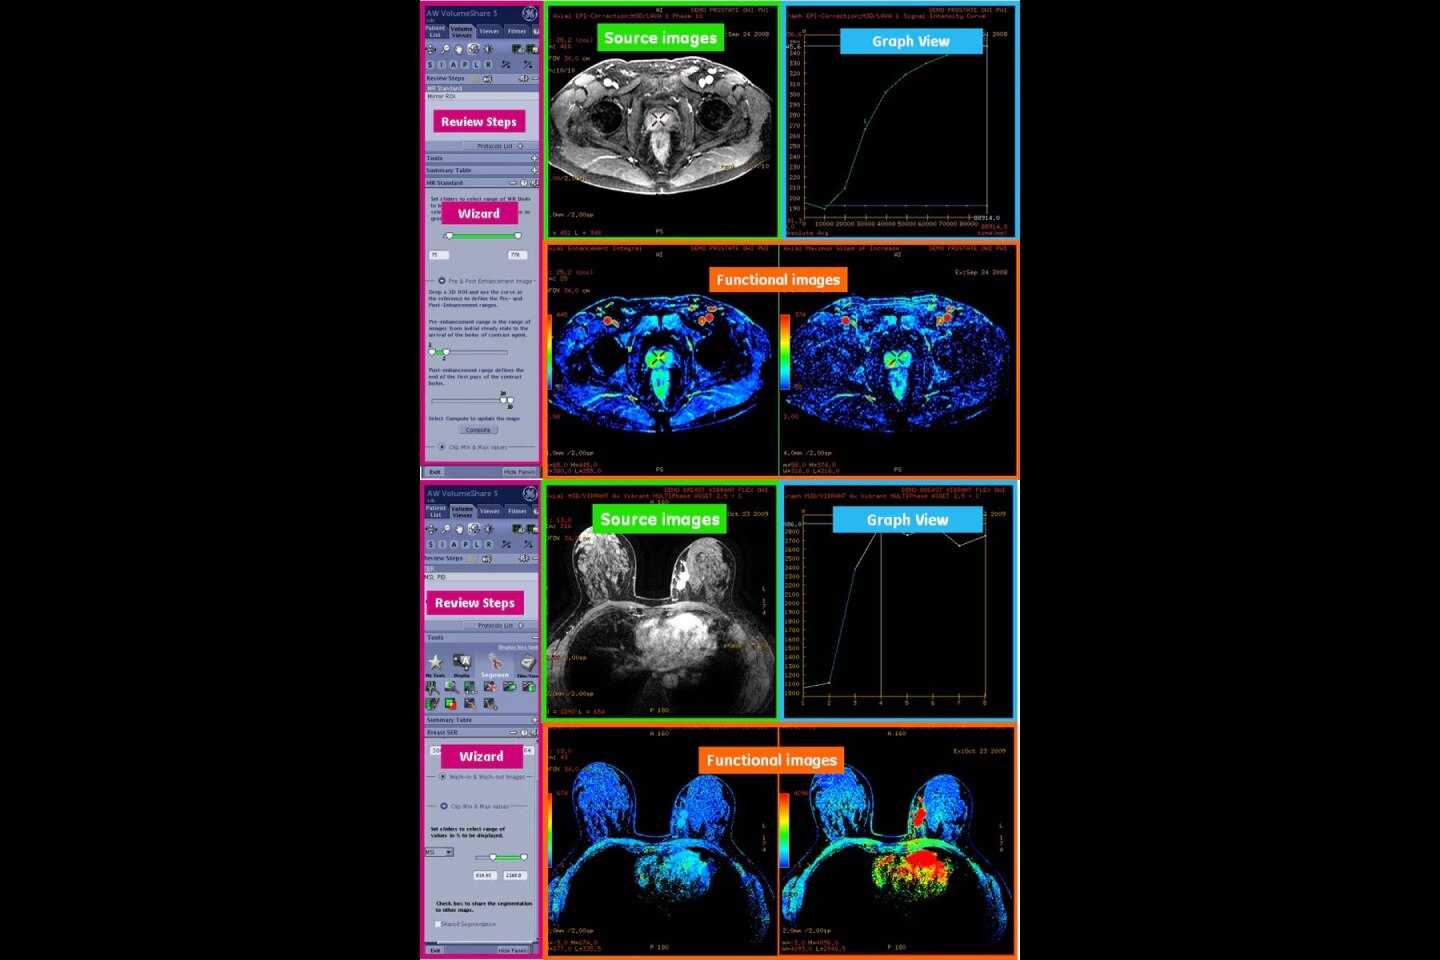

Mappe di perfusione e classificazione dei tessuti

• Soluzione completamente integrata con CT Perfusion 4D per la visualizzazione delle mappe funzionali della perfusione³

• La segmentazione del ventricolo cerebrale con deep learning impedisce l'inclusione della materia ventricolare nei risultati quantitativi e migliora l'analisi delle mappe

• Calcolo automatico delle mappe funzionali

• Mappa di classificazione dei tessuti segmentata da valori assoluti o relativi, con soglie personalizzabili e mappe di input selezionabili dall'utente

• Volume e rapporto di mancata corrispondenza calcolati dalla regione di perfusione modificata e dalla regione con bassa perfusione